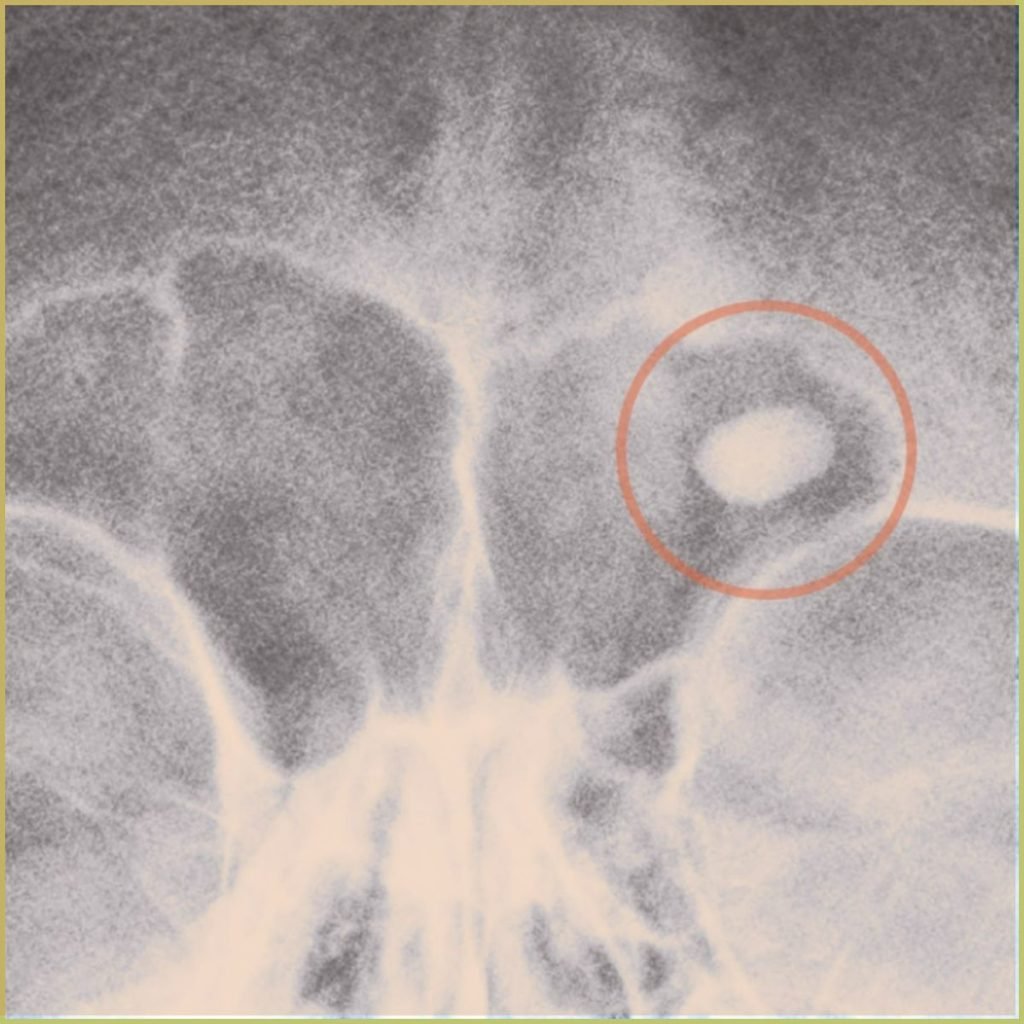

OSTEOMA

Osteoma is a benign slow-advancing bone forming tumor that consists primarily of well-differentiated mature compact or cancellous bone. Maxillary and mandibular tori are not considered osteomas. Osteomas are linked to Gardner’s syndrome. The common clinical presentation includes:

- Round well-circumscribed homogeneous radiodensity.

- May be positioned subperiosteal or medullary.

- Asymptomatic and usually discovered incidentally.

- May cause painless swelling and facial asymmetry.

- Symptoms secondary to nasal/paranasal obstruction include sinusitis, nasal discharge and mucocele formation.

- Symptoms secondary to orbital involvement include exophthalmos, proptosis, ptosis, and diplopia.

Diagnosis is based on the lesion history, clinical presentation and microscopic findings, which usually includes mature bone formation that blends imperceptibly with the underlying normal bone. Your differential diagnosis should include:

- Tori or exostosis.

- Ossifying fibroma.

- Osteoblastoma.

- Focal sclerosing osteitis.

Treatment may not be necessary.